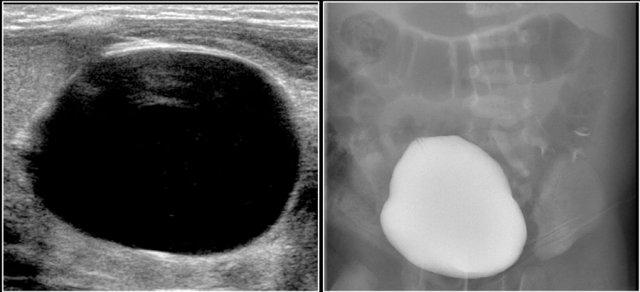

Đây là hình ảnh siêu âm của một bé trai 5 tháng tuổi được phát hiện trước sinh có hệ thống đài bể thận giãn và không thấy niệu quản, phù hợp với hẹp khúc nối bể thận – niệu quản.

Trên mặt cắt dọc, hệ thống đài bể thận giãn được hiển thị rõ ràng.

Một bé trai 1 tuổi được chuyển đến với chẩn đoán u nguyên bào thận dạng nang.

Siêu âm phát hiện một nang lớn ở trung tâm ổ bụng.

Khi khảo sát từ hông trái bằng đầu dò tuyến tính tần số cao, có thể thấy một ít mô nhu mô bao quanh các đài thận giãn rất to. Hình ảnh này phù hợp với ứ nước thận mức độ nặng.

Ban đầu, người ta cho rằng có một số thành phần đặc trong nang.

Tuy nhiên, khi ấn đầu dò, các thành phần này được xác định là cặn lắng.

MRI cho thấy hình ảnh tổng quan hơn về tình trạng ứ nước thận.

Nguyên nhân là do hẹp khúc nối bể thận – niệu quản.

Thận trái có chức năng phân chia 33% trên xạ hình thận.

Phẫu thuật tạo hình bể thận đã được thực hiện thành công.